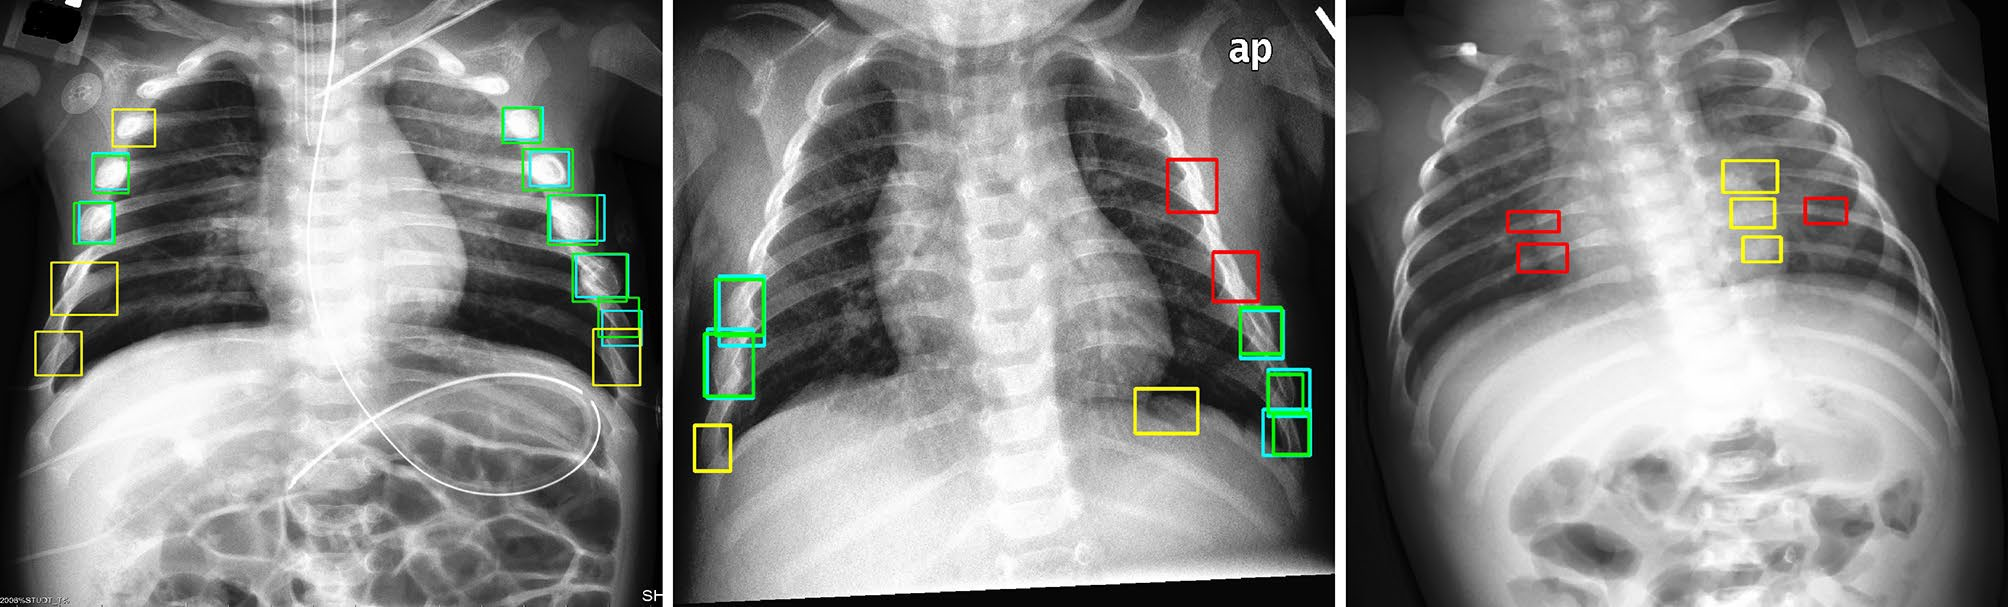

The dataset included at least 60 examinations for each of the following anatomic regions: foot and ankle, knee and leg, hip and pelvis, hand and wrist, elbow and arm, shoulder and clavicle, rib cage, and thoracolumbar spine. When the AI model's "confidence level" for identifying fractures was surpassed, it highlighted regions of interest with a white square box on the radiograph.

A radiograph showing a single true-positive fracture of the right femoral neck (arrows). This fracture was detected by AI using the FRACT threshold (box). The fracture was missed by one senior and one junior radiologist, two emergency department physicians, one physician assistant, three rheumatologists, and one family medicine physician. All readers pointed out the fracture with the assistance of AI. Image courtesy of Radiology.Two experienced musculoskeletal radiologists with 12 and eight years of experience respectively established ground truth by independently interpreting all examinations without clinical information. Only acute fractures were considered to be a positive finding in the study.